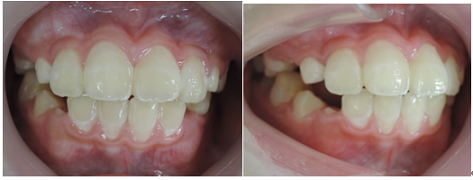

治療前 治療後

この様な歯並びの方はかなり見受けられるとと思われます。

当矯正歯科医院では、咬合バランスを改善する為には、

顎骨の拡大だけでは不十分と考ています。

その為、かみ合わせの高さなど立体的に改善していく事を心がけて日々治療しています。

今回も治療には、独自の方法とビムラー・t4k等を利用して改善しました。

今後、永久歯の歯並びは永久歯が萌えてから改善していく計画です。

顎骨のバランスは良好の為、永久歯を抜歯する必要は全くありません。

矯正前 矯正後

今回も治療には、独自の方法とビムラー装置等を利用しました。

咬合バランスをよくする為には、

顎を大きくするだけでは不十分と考えています。

その為、かみ合わせの高さなどを立体的に改善していく事を心がけて治療しています。